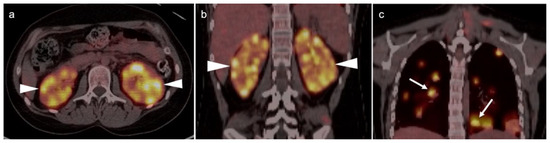

3.1. Prostate Cancer